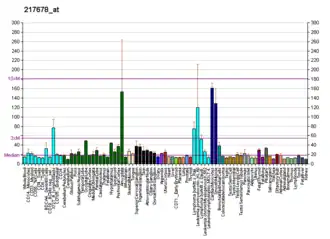

SLC7A11 plays an important role in glutathione production throughout nervous and non-nervous tissues. In the nervous system, SLC7A11 regulates synaptic activity by stimulating extrasynaptic receptors and performs nonvesicular glutamate release. This gene is highly expressed by astrocytes and couples the uptake of one molecule of cystine with the release of one molecule of glutamate. The expression of Xc- was detected throughout the brain with higher expression found in the basolateral amygdala, the retina and the prefrontal cortex. The inhibition of system Xc- has been found to alter a number of behaviors, which suggests that it plays a key role in excitatory signaling.